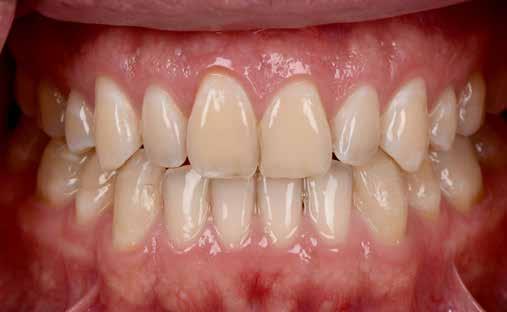

Behelyezés

A fogorvos, fogtechnikus és páciens közötti jó együttműködés kifizetődik, mert a restaurációk a lehető legrövidebb idő alatt, minimális korrekcióval helyezhetők szájba. A klinikai helyzetet, amelyet a mintákon, majd az ideigleneseken keresztül idealizáltunk, a végleges restaurációval is sikerült megvalósítani (13. kép). A páciens és a kezelőcsapat elégedettsége magas szintű volt. A terápia egyenes vonalúnak, sikeresnek bizonyult.

Eredmény

Egy hónap elteltével szép, egészséges képet figyelhettünk meg, ínygyulladás nélkül (14–15. képek). A digi -

tális munkamenet alkalmazása minimális ráfordítással maximális esztétikai eredményt hozott. Az ideiglenes koronák szubgingivális kontúrjának újbóli megvalósítása a végleges pótlással különböző változásokat hozott magával a kezelési folyamat során. Az IPS e.max Press Multi anyag kiemelkedő esztétikai tulajdonságokkal rendelkezik. Ha még ezen felül is egyéniesíteni akarunk, az incizális területet IPS e.max Ceram leplezőkerámiával is kiegészíthetjük (cut-back technika). A bemutatott munkamenet a klasszikus préstechnika kombinálása a számítógép támogatású tervezéssel és gyártással, sok előnyt rejt magában, új kihívásokat jelent, innovatív felhasználást tesz le -